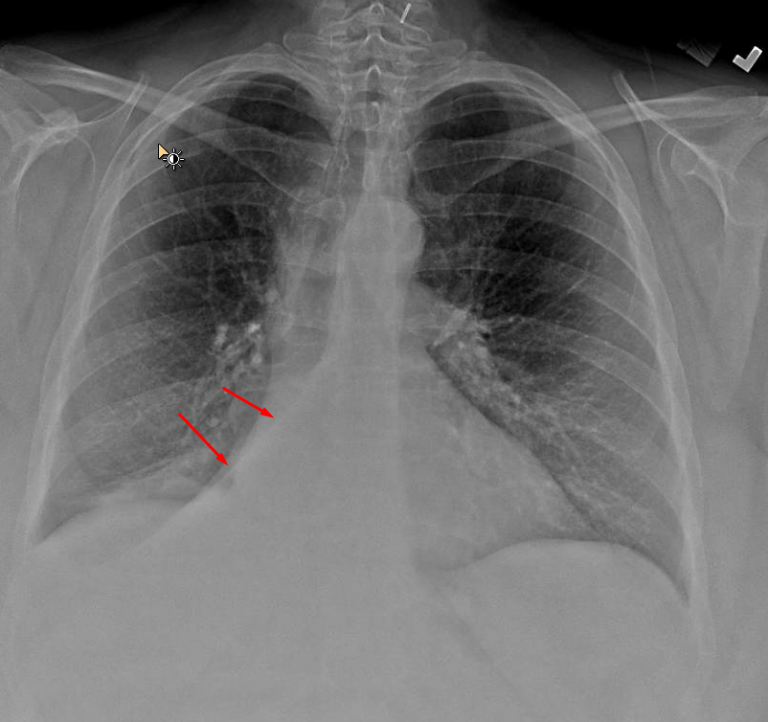

Age: 55

Sex: Female

Indication: Hemoptysis

Sample ReportRight middle and lower lobe collapse. Recommend chest CT to assess for a central obstructing mass.